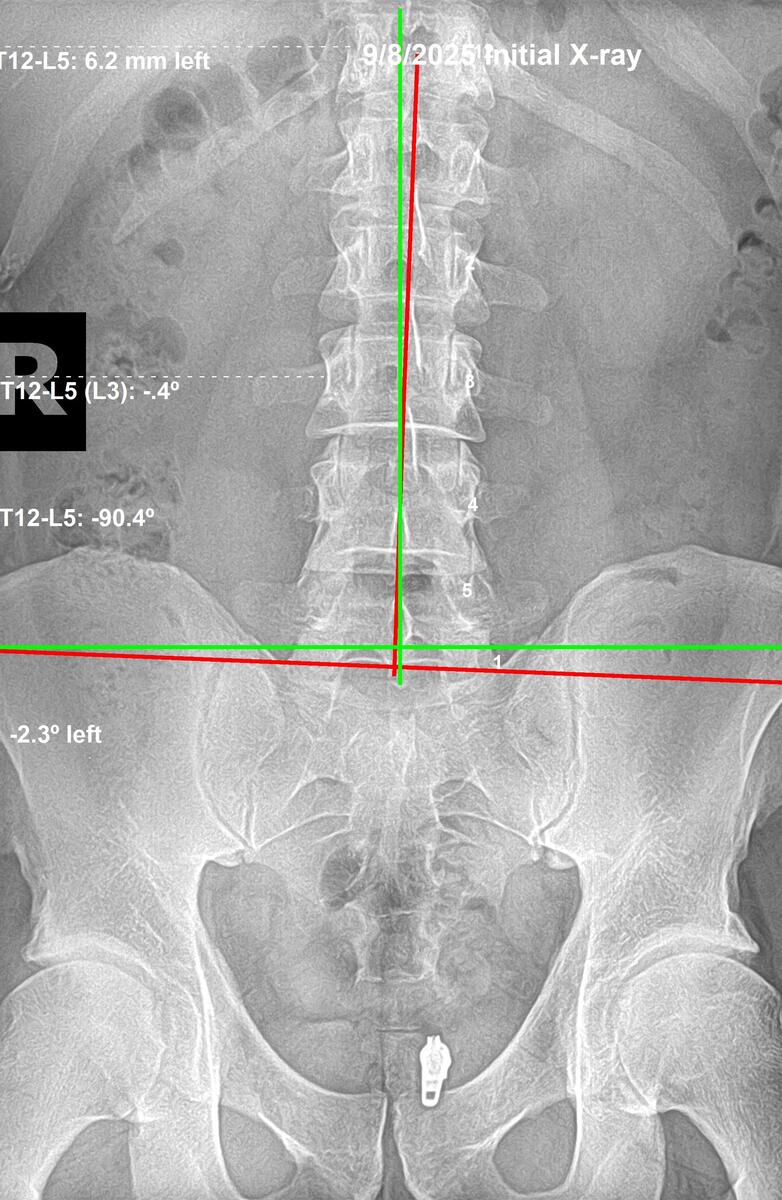

Initial lumbar AP X-ray showing left anterior inferior sacrum at 2.3 degrees, September 8 2025, Rochet Family Chiropractic Royal Palm Beach

Before — Sept 8, 2025

Lumbar (AP): Left anterior inferior (AI) sacrum, 2.3° deviation. Sacral base unlevel, destabilizing lumbar foundation.